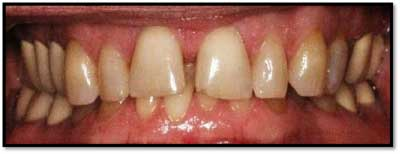

UL/LL Pre TxUL/LL Pre Tx reflected in a mirror

TX FM Perioscopy with local anesthetic FM LANAP Surgical Procedure •bone sounding was performed on all teeth included in this procedure •occlusal adjustment performed resulting in reduction in centric prematurities •Orthodontic referral for anterior spacing •3 month periodontal maintenance14 months post TreatmentPocket reductions of up to 4mm